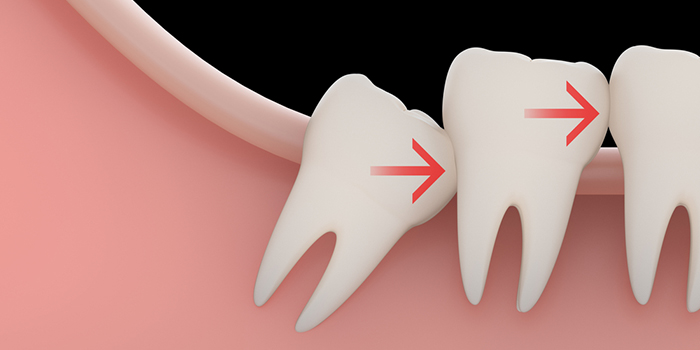

もともと、親知らずが生えるスペースは狭いものです。

このため、親知らずはななめに生えたり、横向きに生えたりしやすく、周囲の歯を押してしまうことがあります。

この結果、歯並びやかみ合わせが悪くなってしまうこともあるのです。